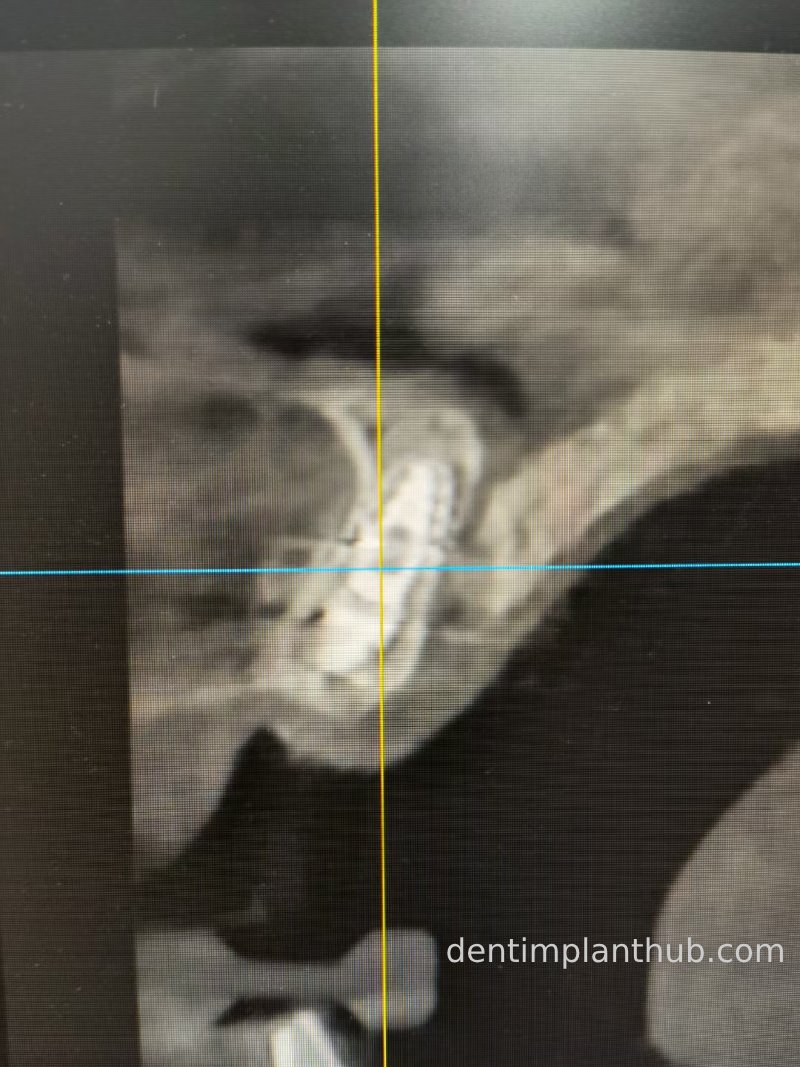

Three-dimensional CT images after surgery

21 Postoperative CT screenshot